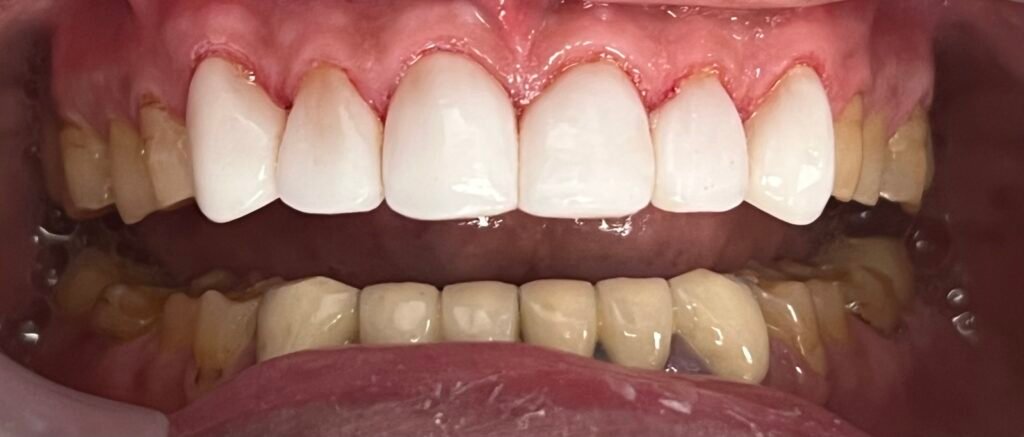

Stop the progression of gum disease and preserve your natural teeth with Gum treatment in Sunnyvale at Huh Dental Wellness

Our specialists remove plaque and calculus from above and below the gum line, smoothing the roots to encourage the gum tissue to reattach to the teeth.

A beautiful smile is only as strong as the foundation it sits upon. Our periodontal team is dedicated to ensuring that foundation remains healthy, resilient, and life-long.